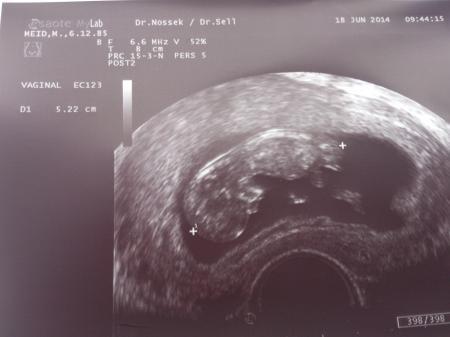

und es ist als super und zeitgerecht, Herz schlägt, es hat sich munter bewegt und fa hat kein Hinweis auf nackenödem

ach ja heute 11+5, und Krümel 5,2cm!

Bild